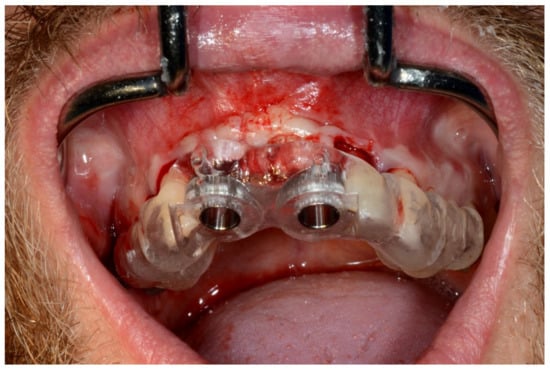

Figure 22.

Maxillary surgical drilling guides temporarily supported and fixed with mini-screws.

Figure 23.

Mandibular surgical drilling guides temporarily supported and fixed with mini-screws.